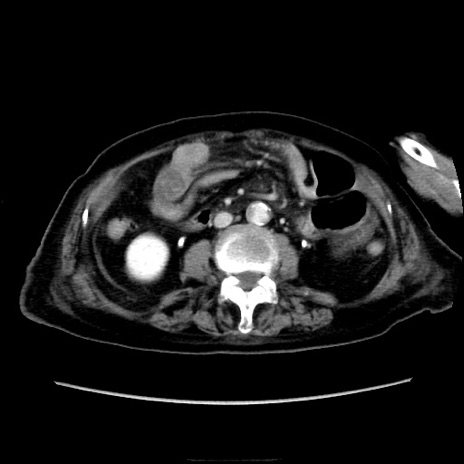

他院CT

冠状断像